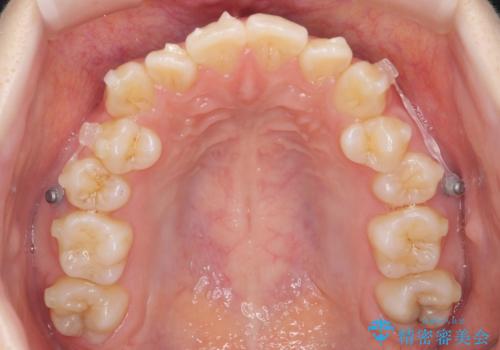

下の八重歯 歯を抜かずに インビザライン治療

- 歯並びのがたつきを主訴に来院。

抜歯してワイヤー矯正という選択肢も提案しましたが、マウスピース矯正で、歯を抜かずに並べてほしいとのことでした。

スペースを確保するために、歯をわずかに削る処置、奥歯を後ろに下げる処置(インプラント矯正)を行っています。

途中患者様のご都合で治療を中断していたため、長くかかっていますが、実質2年程度で終わる内容でした。